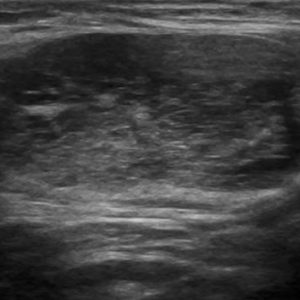

U tuyến nước bọt

Lượt xem: 131» 19-01-2021 -